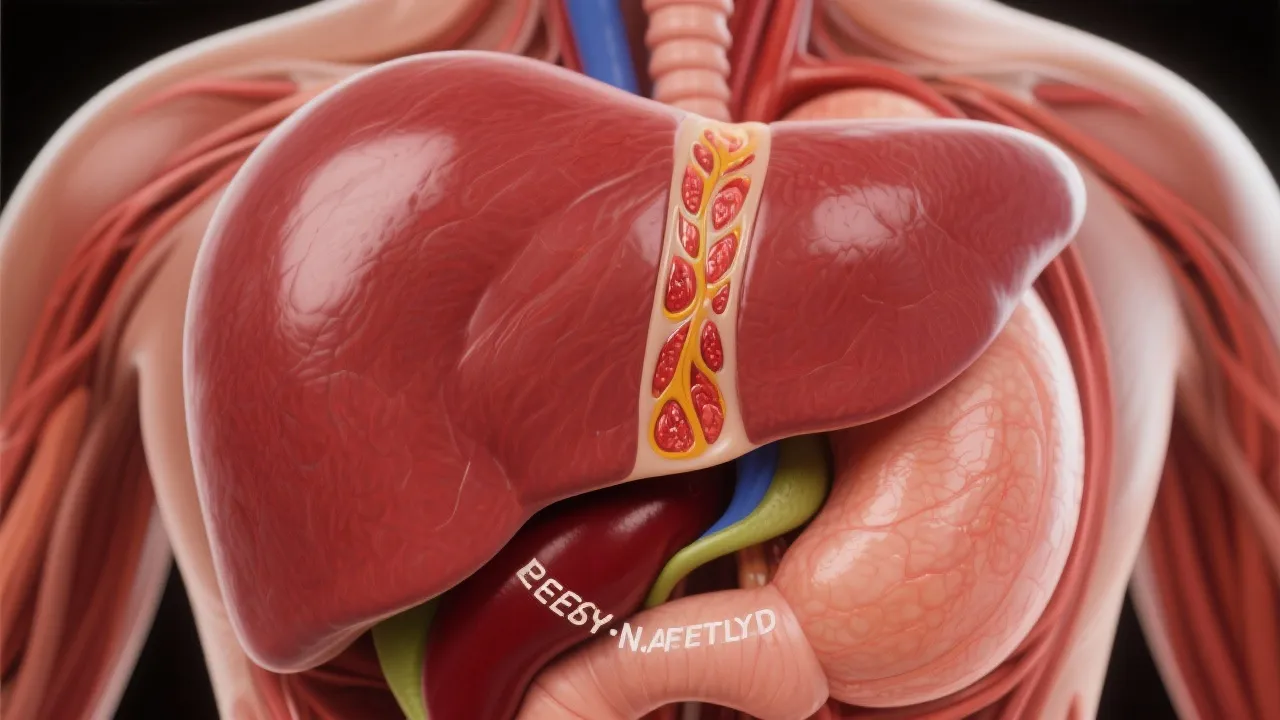

In recent decades, the prevalence of obesity has risen alarmingly worldwide, coinciding with a surge in Non-Alcoholic Fatty Liver Disease (NAFLD). NAFLD is a major public health concern characterized by the accumulation of fat in liver cells, which is not caused by excessive alcohol intake. Understanding the intricate relationship between obesity and NAFLD is critical, particularly given the progressive nature of NAFLD, which can lead to severe liver conditions such as cirrhosis and hepatocellular carcinoma. The World Health Organization (WHO) has recognized obesity as a global epidemic, with millions of people affected, leading to severe health complications. The alarming statistics regarding obesity and its association with NAFLD have prompted researchers and healthcare professionals to investigate this connection further, revealing complex interactions between genetic, environmental, and lifestyle factors.

Obesity is one of the very significant risk factors for NAFLD, accounting for an estimated 80-90% of NAFLD cases. Excess body fat changes metabolic profiles, promoting insulin resistance, a key player in hepatic fat accumulation. Furthermore, obesity-related inflammation contributes to liver damage and fibrosis. In addition to the visceral fat surrounding organs, subcutaneous fat also plays a contributing role in metabolic dysfunction. Studies show that the type and distribution of body fat can influence the severity of liver disease. This connection is primarily mediated through various hormonal and biochemical pathways, whereby excess adipose tissue releases free fatty acids and inflammatory cytokines into the bloodstream, further exacerbating liver injury. Understanding these links highlights the need for targeted interventions to tackle both obesity and subsequent liver complications.

The pathogenesis of NAFLD in obesity involves multiple metabolic pathways. Insulin resistance boosts lipolysis, leading to increased affordable fatty acid delivery to the liver. This exacerbates hepatic fat accumulation while also impeding very low-density lipoprotein (VLDL) secretion. Insulin also plays an essential role in glucose metabolism, and elevated insulin levels can lead to a decrease in the activity of enzymes responsible for fatty acid oxidation in liver cells. Notably, the interaction between elevated insulin levels and increased fatty acid production creates a vicious cycle that accelerates the progression of NAFLD. Additionally, an imbalance in adipokines, hormones produced by adipose tissue, furthers liver inflammation and damage. Leptin, an adipokine that is elevated in obesity, is known to promote inflammation and disrupt the balance of normal metabolism in the liver.